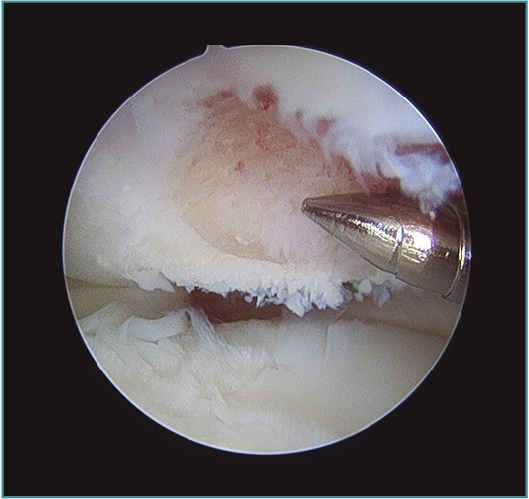

Pueden ampliarse los portales 1 cm a modo de mini-open para facilitar la extracción del fragmento libre articular o la fijación del mismo si fuera necesaria (Figura 7). Una vez extraído el cuerpo libre, se puede refrescar la zona origen del defecto con un sinoviotomo o incluso realizar unas perforaciones con un punzón o una aguja de Kirschner de 1,8-2 mm, con una separación entre ellas de 2-3 mm aproximadamente, para favorecer la creación de un tejido fibrocartilaginoso que proteja la zona (Figuras 8 y 9)(10). Por esta misma vía se pueden realizar técnicas complementarias como la introducción de matrices celulares o biogeles (véase más adelante).

Figura 8. Desbridamiento de una lesión osteocondral en la porción inferior del capitellum y perforaciones. Visión desde portal mediolateral directo.